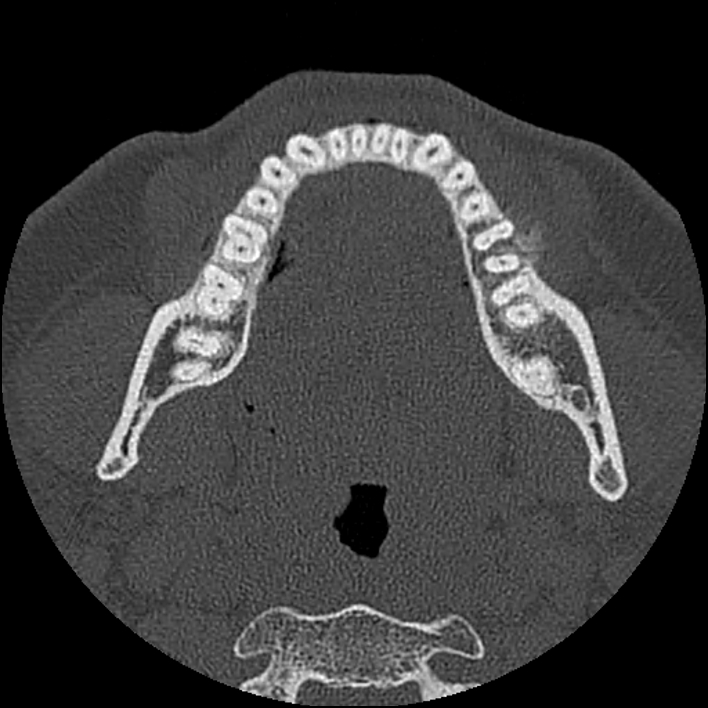

Figure 4 for case Chondroblastic osteosarcoma of the mandible

Figure 4